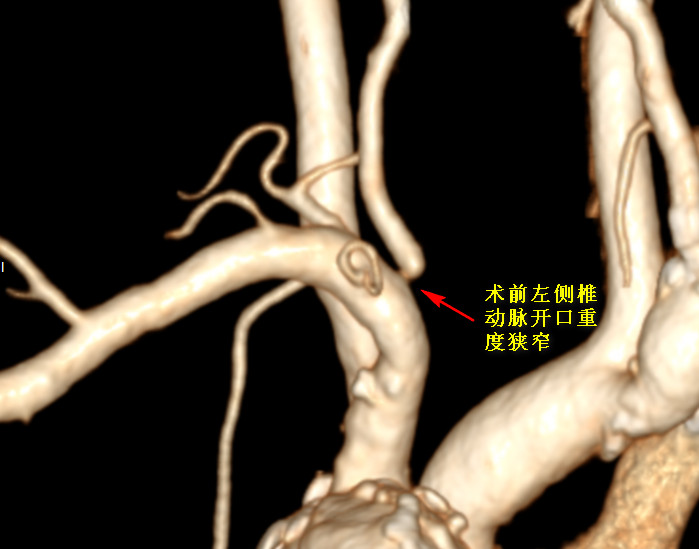

来到医院神经外科就诊时,头颈部血管 CTA 检查提示:他的右侧颈内动脉分叉部重度狭窄;双侧椎动脉开口狭窄。也就是说杨老伯供应大脑血运的四根血管里面已经有三根狭窄了,现在就靠一根血管强撑着,还随时可能出现完全阻塞不通的情况。这唯一的生命通道一旦阻塞,就会发生人们常说的「中风」(脑卒中),后果不堪设想。

其实,杨老伯以前就患过脑梗塞,还有 2 型糖尿病、高血压这些病史,健康状况不容乐观。针对他的特殊情况,神经外科贾军主任组织科内团队成员进行全面讨论、病情评估,确定杨老伯的症状都是由双侧椎动脉开口狭窄造成的脑组织后部循环缺血造成的,决定为他发生狭窄较重的右侧椎动脉开口施行药物涂层支架置入术,为大脑恢复足够量的血流供应,拓宽杨老伯的生命线。